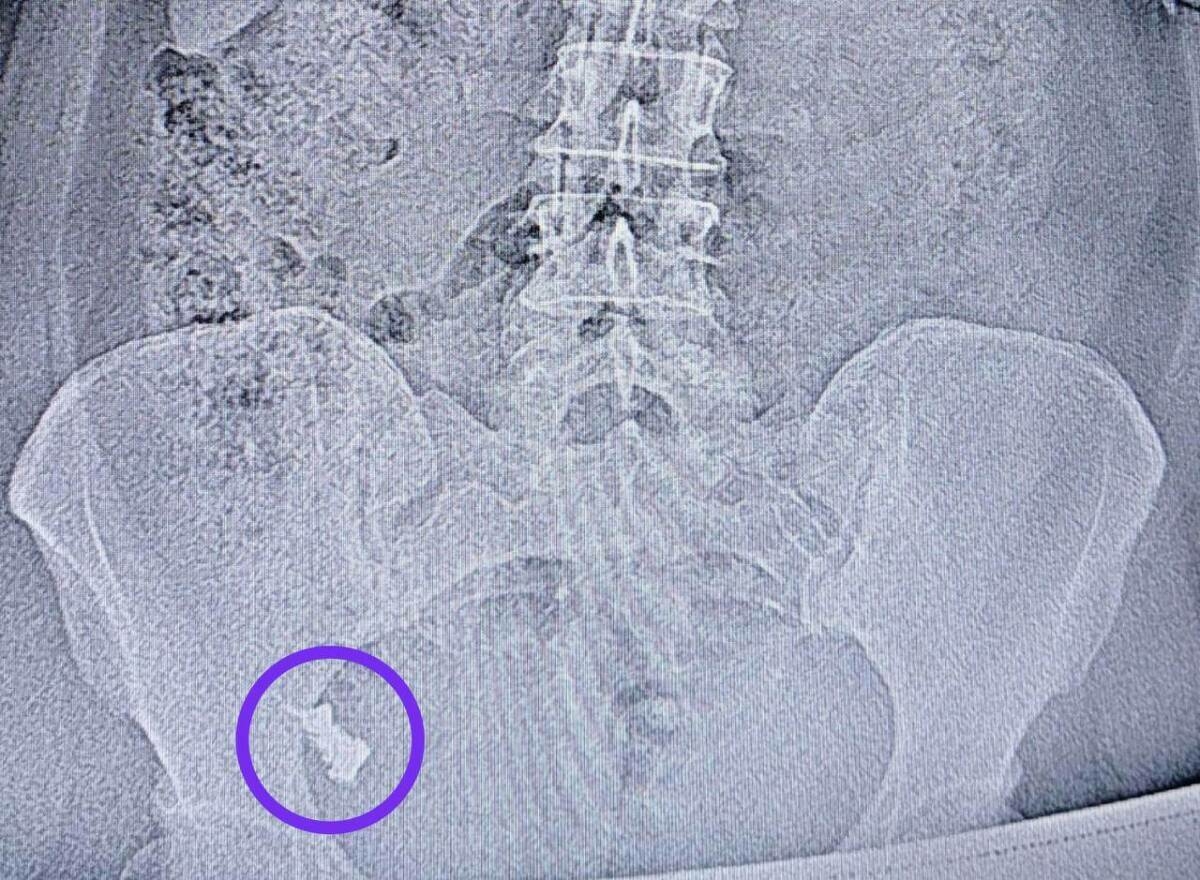

Бер атнадан аны 1 нче хирургия бүлегенә салганнар, чөнки протез нечкә эчәклек юан эчәккә күчә торган урында кысылып калган.

Табиб-эндоскопист Наил Исхаков колоноскопия вакытында протезны чыгарган. Процедураны анестезиолог-реаниматолог Елена Чуенкова контролендә уздырганнар, чөнки протез авыр керә торган урында булган. Анестезия белән процедура авыртусыз узган.